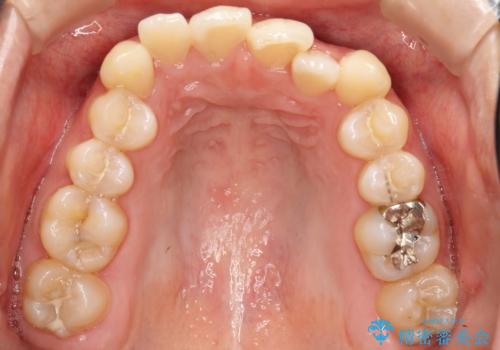

初診時の歯並びの状態としては、上下ともに全体に及ぶの中等度以上のがたつき(叢生)があり、前歯数本が反対交合の状態でした。

強い叢生がありましたが、抜歯は行わず上下顎ともに、主に歯列弓の拡大とディスキング(歯と歯の間に隙間を作る処置)を行い叢生を改善しました。